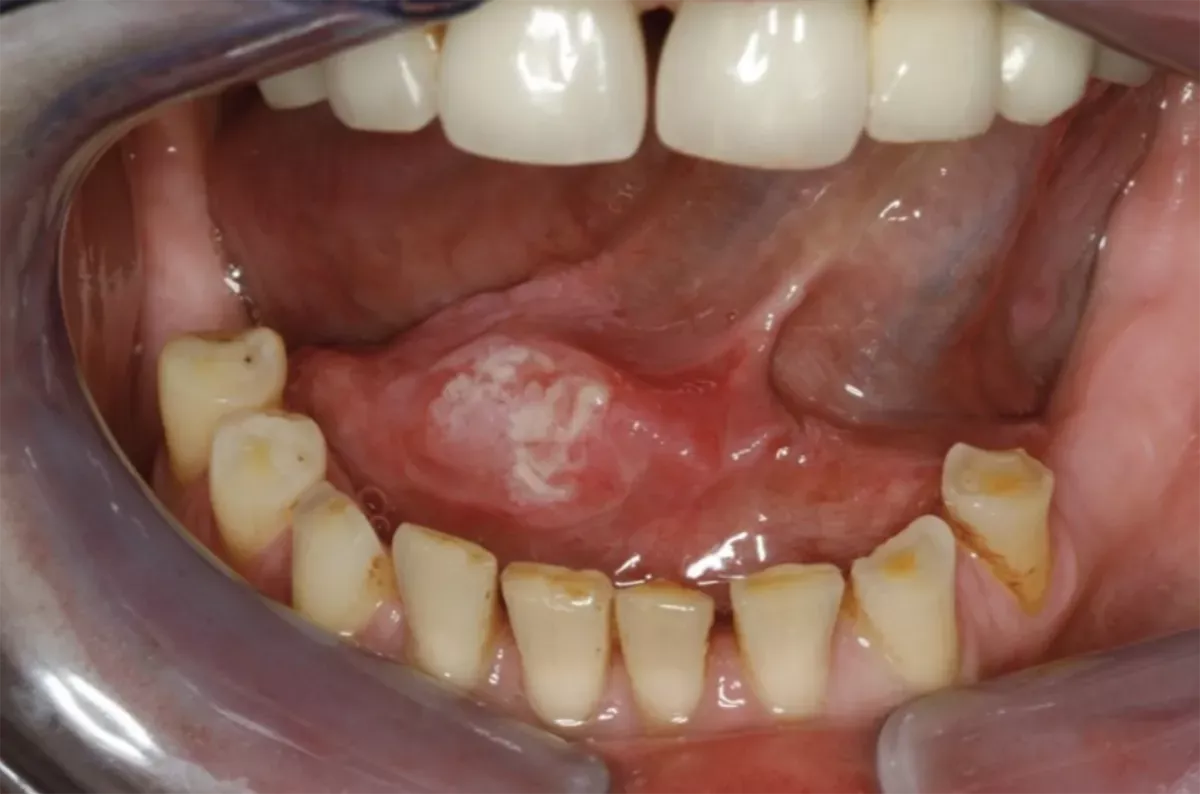

What does floor of the mouth cancer look like?

The following images provide a rough idea of what floor of the mouth cancer actually looks like. Note, however, that every tumour appears different. If you detect a suspicious spot on the floor of your mouth, have it checked by a doctor to rule out floor of the mouth cancer – regardless of whether it is a lump, an ulcer, a white or red patch or a sore. Aphthae can also look very similar but typically resolve on their own after one to two weeks without the need for treatment. If the affected area fails to heal, it is best to go and see a health care professional.